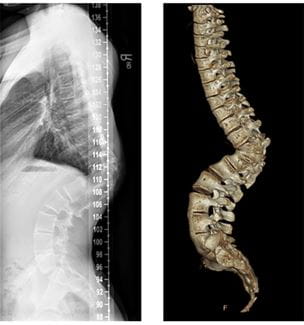

UH Rainbow Division of Pediatric Orthopaedic Surgery Embraces Complex Cases, Adds Advanced X-ray System

Vertebral column resection likely most complex ever performed in Northeast Ohio - Innovations in Pediatrics | Winter 2021